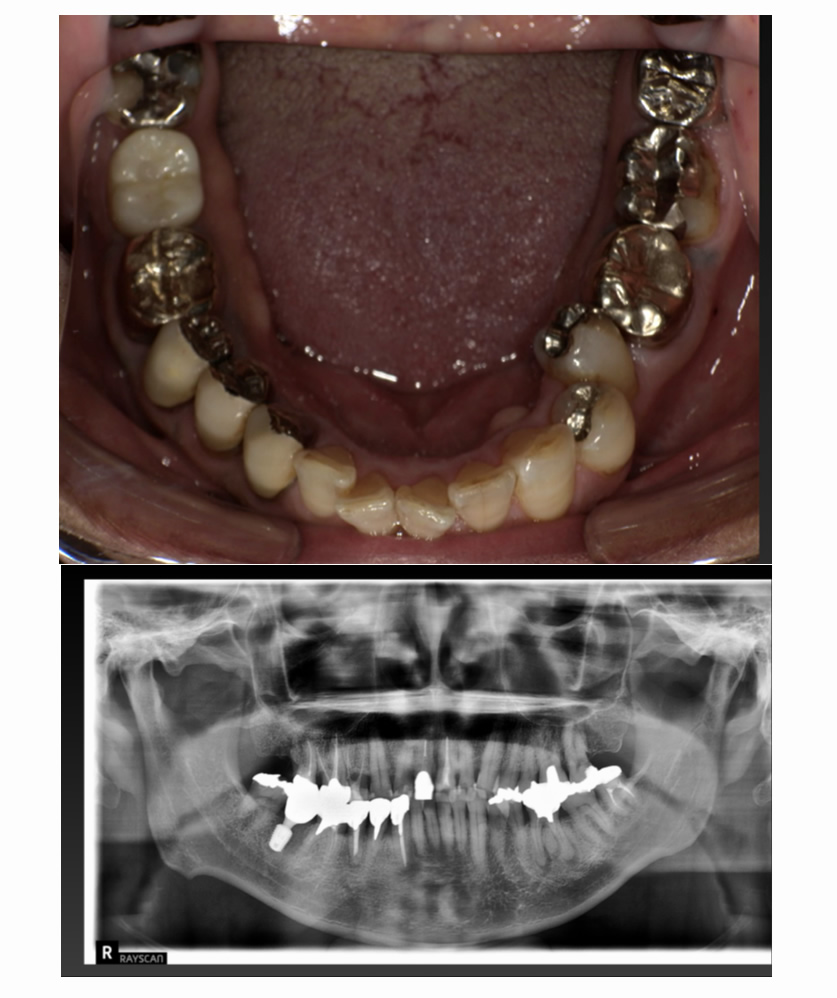

04 症例

04 右下の歯が割れ、左上が入れ歯なのでインプラント希望

Before

After

| 治療内容 | 右下の歯が割れている、左上が入れ歯なのでインプラント希望 |

| 患者さま | 50代男性 |

| 主訴 | 根が割れていて痛いのと、入れ歯の管理が大変なのでインプラントにしたい。 |

| 治療期間(目安) | 3ヶ月 |

| 治療費(税込:目安) | ¥984,500 |

| リスク | 術後に多少の痛みや腫れが出ることがある。歯肉退縮がおきると、歯と歯肉の間に隙間が生じることがあります。 |